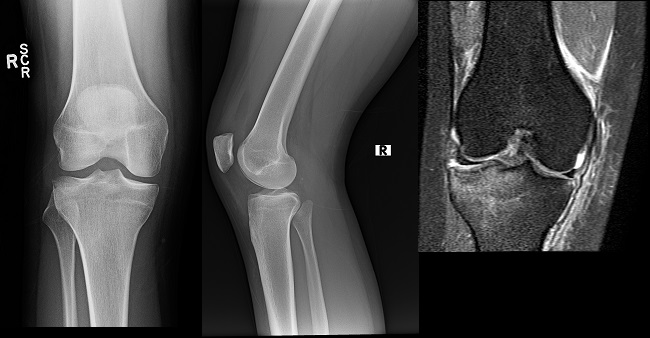

An 80 year old female presents to your office with a left ring finger deformity after a fall one week ago. She initially went to urgent care and xrays were unremarkable for a fracture (Figures 1 and 2). A photo of her left ring finger is shown in figure 3. On physical exam the left ring finger is in hyperextension at the PIP joint and flexion at the DIP joint. She able to flex her PIP joint with full motion. What is the best treatment option?